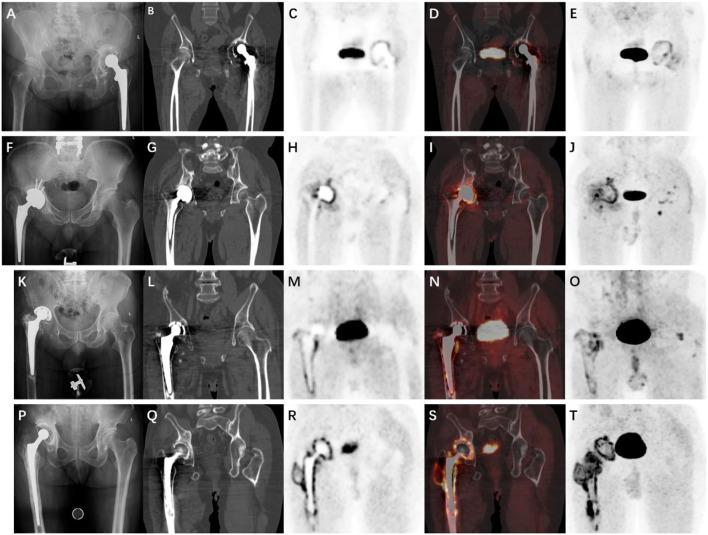

This case report describes four patients with symptomatic total hip arthroplasty (THA), two cases of loosening and two cases of infection. Although the four cases were correctly diagnosed by the tissue culture, preoperative tests and pathological examination could not effectively distinguish an infection from a non-infection. Based on a preclinical study and theoretical feasibility, gallium-68 (Ga)-labeled fibroblast activation protein inhibitor positron emission tomography/computed tomography (Ga-FAPI PET/CT) was performed. Through Ga-FAPI PET/CT scanning, not only were the causes diagnosed correctly but the lesions were also located.

When the lesion is located between the bone and the prosthesis, Ga-FAPI PET/CT could differentiate aseptic loosening from periprosthetic joint infection (PJI). Ga-FAPI PET/CT has clear advantages over routine examinations and has a prospective application in detecting PJI.

本病例报告描述了4例有症状的全髋关节置换术(THA)患者,其中2例为松动,2例为感染。尽管这4例均通过组织培养得以正确诊断,但术前检查和病理检查无法有效区分感染与非感染情况。基于临床前研究和理论可行性,进行了镓-68(Ga)标记的成纤维细胞激活蛋白抑制剂正电子发射断层扫描/计算机断层扫描(Ga-FAPI PET/CT)检查。通过Ga-FAPI PET/CT扫描,不仅正确诊断了病因,还确定了病变位置。

当病变位于骨与假体之间时,Ga-FAPI PET/CT能够区分无菌性松动与人工关节周围感染(PJI)。Ga-FAPI PET/CT相对于常规检查具有明显优势,在检测人工关节周围感染方面具有前瞻性应用价值。